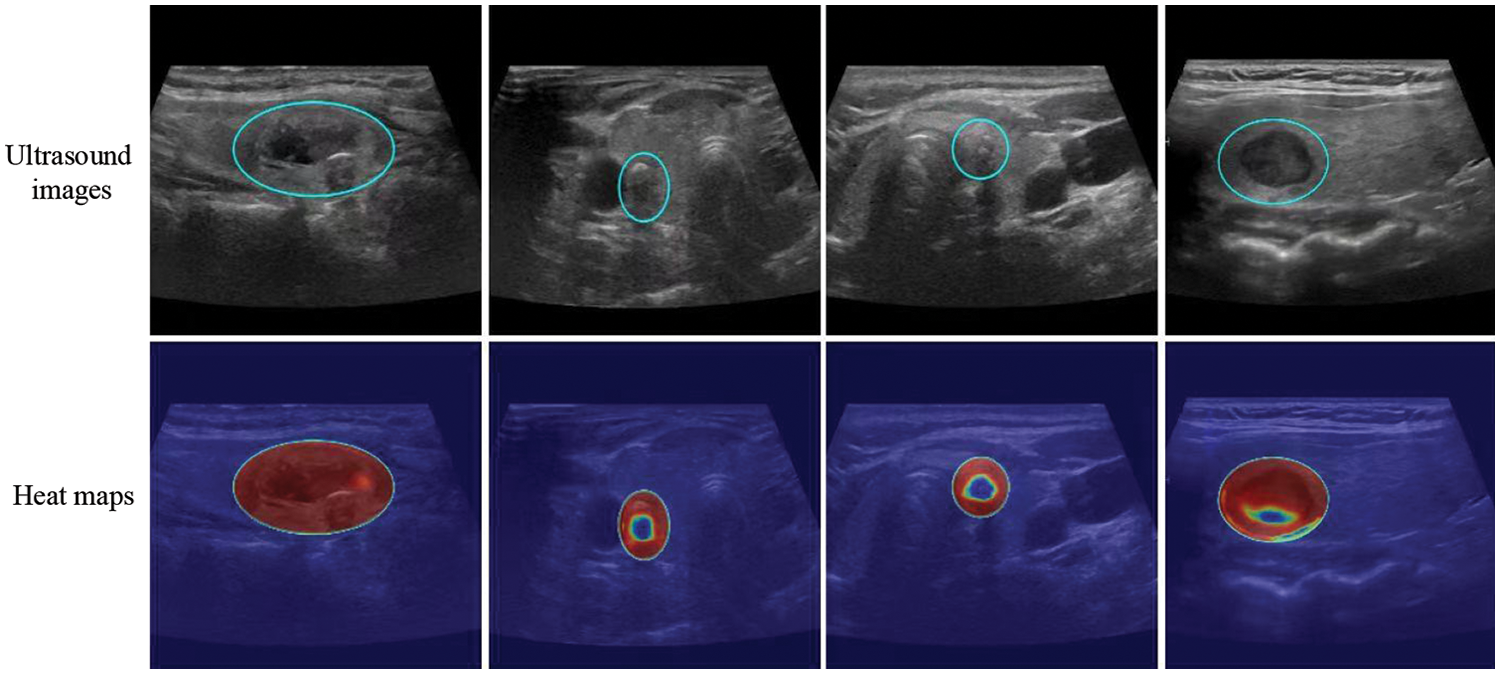

The model successfully focused on the thyroid nodule areas in the ultrasound images. As seen in Figs. 4 and 5, the blue box area denotes the thyroid nodule location, and the heat map represents the visual location result.

Figure 5: Localization of thyroid nodules. The blue circle is the location of the thyroid nodules, and the heat map represents the visualization results. Each column shows the same ultrasound image. The cold tone region of the visualization image is the most important part that our model could recognize